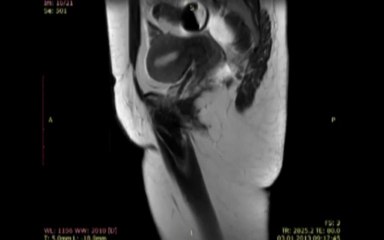

br Prof. Dr. Kayıhan Günay br MR Dekografi işleminin video görüntüleri.